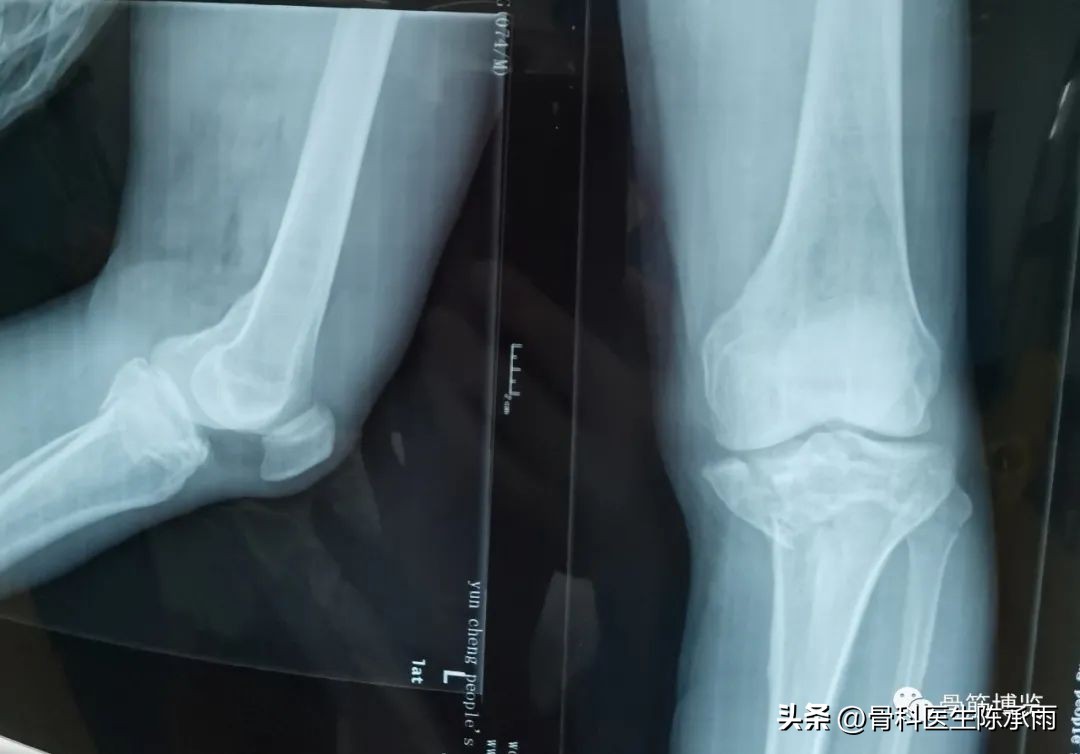

1例

2例

3例

4例

5例

6例

7例